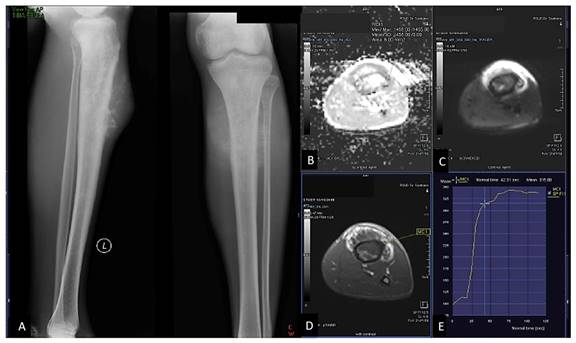

Figure 3

19 years-old man, with osteoblastic osteosarcoma histopathologically in proximal left tibia. X-ray left knee AP projection (A). A single ill-defined osteolytic lesion in diaphysis of proximal left tibia. Restricted diffusion on DWI and ADC map (B,C) with ADC value 0,955 x 10-3 mm2/s, on Dynamic Contrast Enhancement show early contrast enhancement followed by wash out pattern / TIC type 4 (D,E) with %slope result was 19,18 %/s.

In general, malignant tumor has much vascularity and narrow extravascular or interstitial space. Thus, it exhibited rapid and high contrast enhancement 2,25. Tucbilek et al (2004) stated that the steepest lope value accurately reflects tumor vascularization, the malignant soft tissue tumor showed early elevation signal intensity and steepest slope e.g. liposarcoma 28. Two cases of chondroblastic and osteoblastic OS with the presented of ADC value mapping and TIC on DCE were described on Figure 1 and Figure 2.